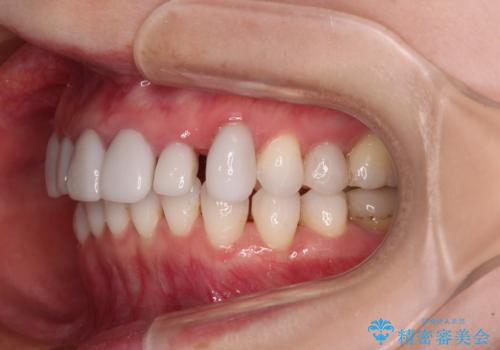

前歯のデコボコと奥歯の咬み合わせをインビザラインで改善

- 上下前歯のデコボコと奥歯の欠損を気にして来院された患者様です。

右下の欠損分は奥歯が倒れ込んでスペースがなくなっていたため、矯正治療により本来の位置に歯を移動させ、オールセラミックブリッジによる欠損補綴治療を行うこととしました。

全顎的にセラミッククラウンが多く装着されているため、インビザラインによる矯正治療を行うこととしました。

右下は移動量が多いため、十分な移動が達成されない場合はワイヤー装置を使用する予定としておりましたが、しっかりとマウスピースを装着してくださったため、前歯とともに十分に歯を動かすことができました。